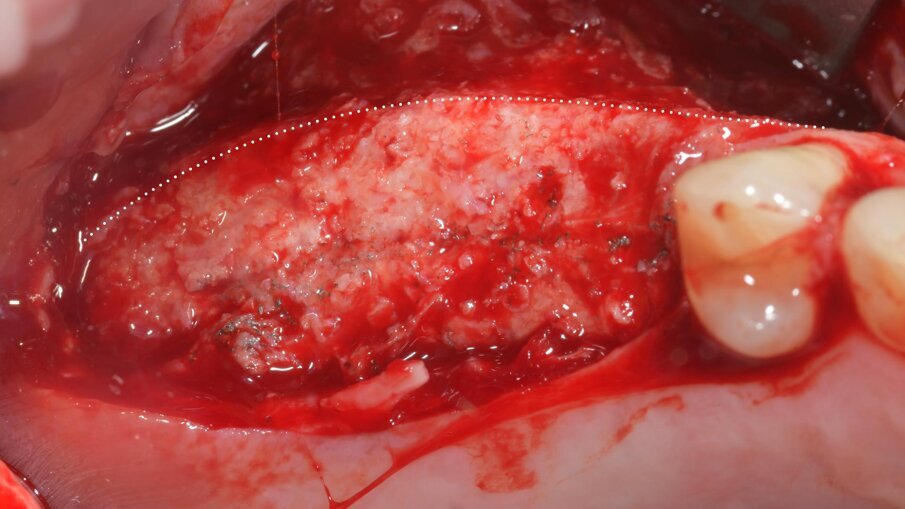

Successivamente, la griglia in titanio customizzata CAD/CAM (Yxoss CBR, Reoss, Geistlich) è stata prelevata dalla doppia busta sterile ed è stata riempita con il materiale da innesto (Fig. 16). La griglia è stata quindi posizionata in sito e fissata con quattro viti di osteosintesi, al fine di ottenere una stabilità assoluta (Fig. 17). È stata poi ricoperta da una membrana riassorbibile in collagene nativo (Biogide, Geistlich) stabilizzata a sua volta con chiodini in titanio (McBio, Geist-lich) (Fig. 18). Prima della chiusura del lembo primario, è stato isolato, prelevato, e avanzato il tessuto grasso della bolla di Bichat, per ridurre il rischio di esposizione e infezione della griglia sottostante17, essendo un tessuto estremamente ricco di cellule pluripotenti, in grado di differenziarsi per la guarigione di prima intenzione dell’area trattata (Fig. 19). Infine, i lembi chirurgici buccale e vestibolare sono stati suturati mediante una doppia linea di sutura, la prima costituita da punti a materassaio orizzontale, la seconda da punti singoli o doppi (Resorba Glycolon, Osteogenics) (Fig. 20). I lembi chirurgici sono stati accuratamente adattati per una chiusura per prima intenzione, senza tensioni, utilizzando una combinazione di suture a materassaio orizzontali e suture interrotte (Resorba Glycolon, Osteogenics) (Figg. 20, 21). Dopo l’intervento chirurgico, la paziente ha seguito un protocollo postoperatorio che includeva una terapia antibiotica (1 g di amoxicillina con acido clavulanico e 250 mg di metronidazolo ogni 8 ore per 7 giorni), e la disinfezione del cavo orale mediante risciacqui con clorexidina 0,2% per 2 minuti, tre volte al giorno, per 14 giorni.